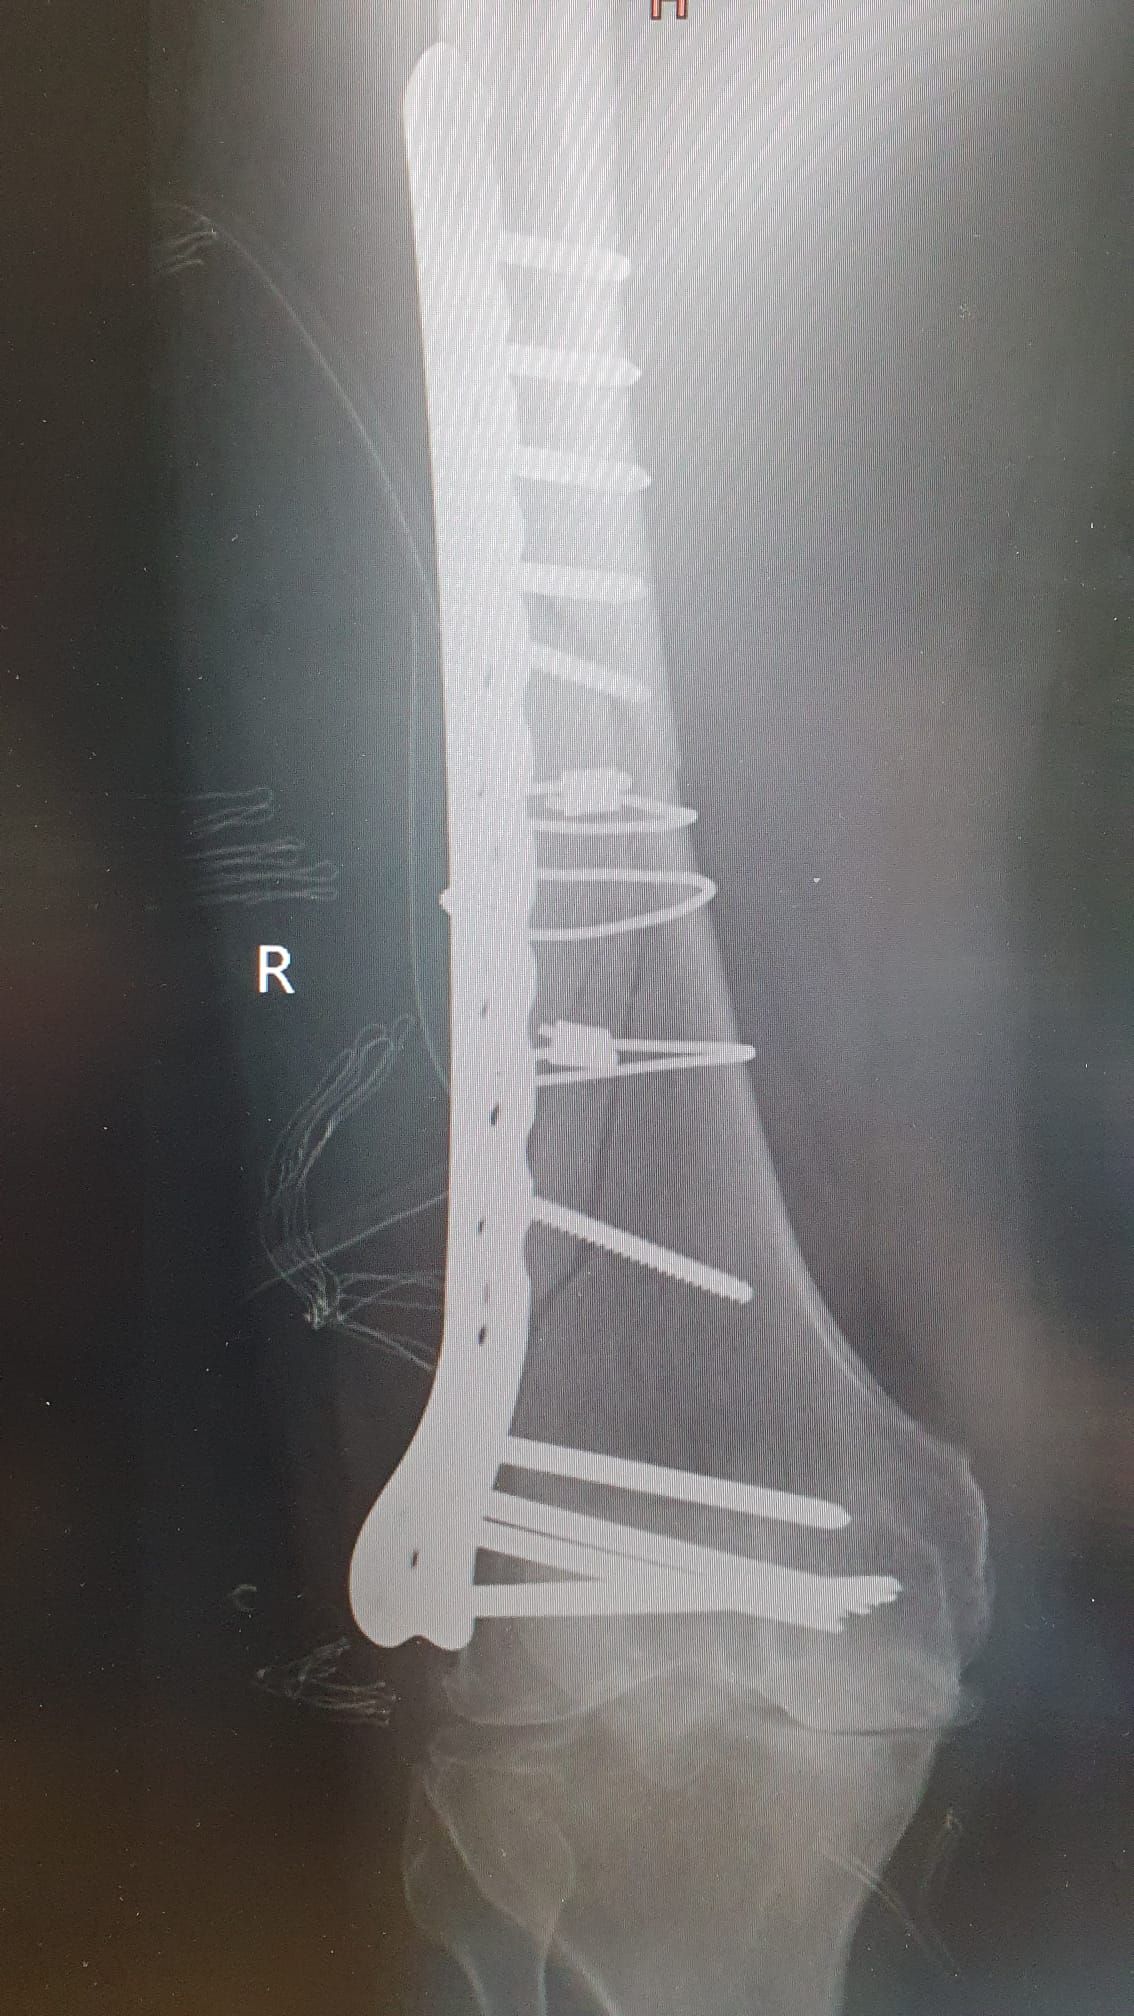

Osteotomie korekcyjne po złamaniach części dalszej kości promieniowej.

Złamania kości. Skręcenia i zwichnięcia stawów.

Zdjęcia i filmy